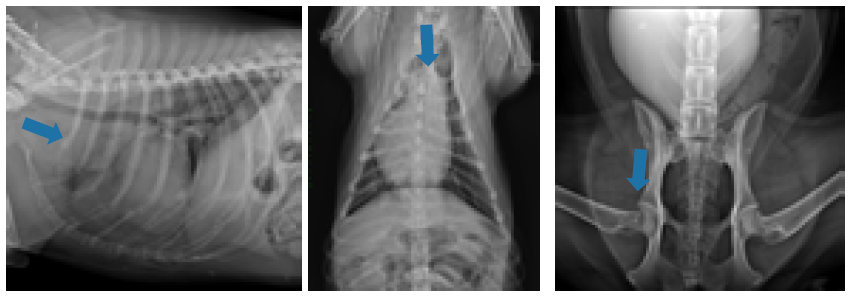

Los linfomas son el tercer tumor intracraneal secundario más frecuente en el perro, siendo la mayoría de los casos secundarios y asociados con enfermedad sistémica.1 Su localización en el encéfalo depende del tipo de patrón, pudiendo afectar a diferentes estructuras, tanto intra como extraparenquimatosas, siendo en muchos casos multifocales.2 La localización en la región selar es excepcional y solo hay dos casos publicados con afección de la hipófisis.3 En este trabajo se describen los signos clínicos, hallazgos de pruebas por imagen y tratamiento de una perra con una metástasis intracraneal de un linfoma con infiltración extensa de la región selar.

La paciente, una perra Bóxer hembra no castrada de 6 años, fue atendida por presentar un cuadro de cojera de la extremidad posterior derecha de una semana de duración que había mejorado parcialmente con el tratamiento con antiinflamatorios no esteroideos, pero que en los últimos dos días había empeorado y también mostraba tendencia a caminar en círculos y deambular. La presencia de dolor a la extensión de la cadera derecha y a la palpación de la región lumbar craneal fueron las únicas alteraciones en la exploración física general. En el examen neurológico se observaron deficiencias compatibles con una lesión en prosencéfalo derecho: marcha en círculos hacia la derecha, retraso en las reacciones posturales en el lado

izquierdo, disminución de la reacción de amenaza y sensibilidad nasal en el lado izquierdo.